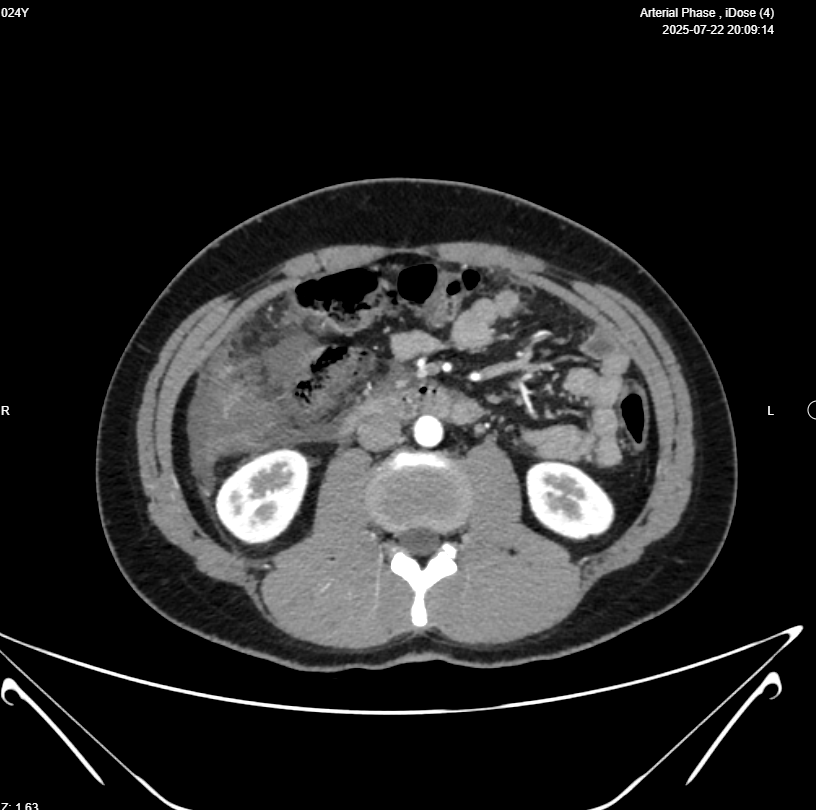

Right iliac fossa presence of Blind loop small bowel mass 39x16mm (Appendicitis ?) , associated with heterogenous mass 112x53mm , in the right sided sub-hepatic region, also associated with dilated bowel loop 26mm (ilieus?) & free intrabdominal fluid >100cc , picture mostly of ruptured viscus appendix ? with its sequel ?? , please for further study

Abdominal CT With IV Contrast

Clinical data: Appendicular mass.

- Evidence of 9 X 8 X 4cm Rt abdominal collection from Rt subhepatic region to RIF, contains fluid and gas, suggestive of an abscess, mostly from perforated appendix.

- Appendix shows diffuse wall thickening, diameter 11mm, with 2.5 X 2.5cm heterogeneously enhanced part in its tip which is in lower part of above mentioned collection, contains few calcifications, which raise suspicion of mucinous tumor.

- Marked inflammation in Rt subhepatic, paracolic gutter, which is surrounding cecum and ascending colon.

- Mild ascites.

- Several mesenteric LNs, mostly inflammatory.